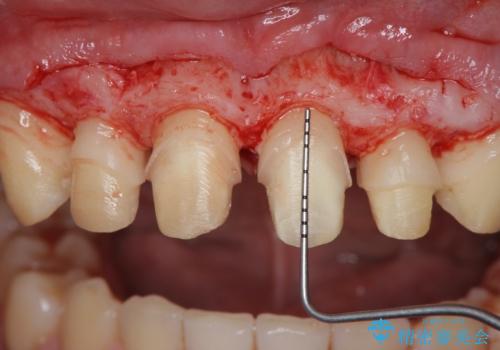

ただ、白いオールセラミッククラウンを製作・装着するのではなく、将来にわたり安定した状況を獲得するため、歯周外科を行い歯ぐきと周囲の歯槽骨の形態を整えていきます。

歯周外科を行ったことで、歯ぐきの形態や腫れが改善され、審美性だけでなく清掃性も大きく改善することができました。